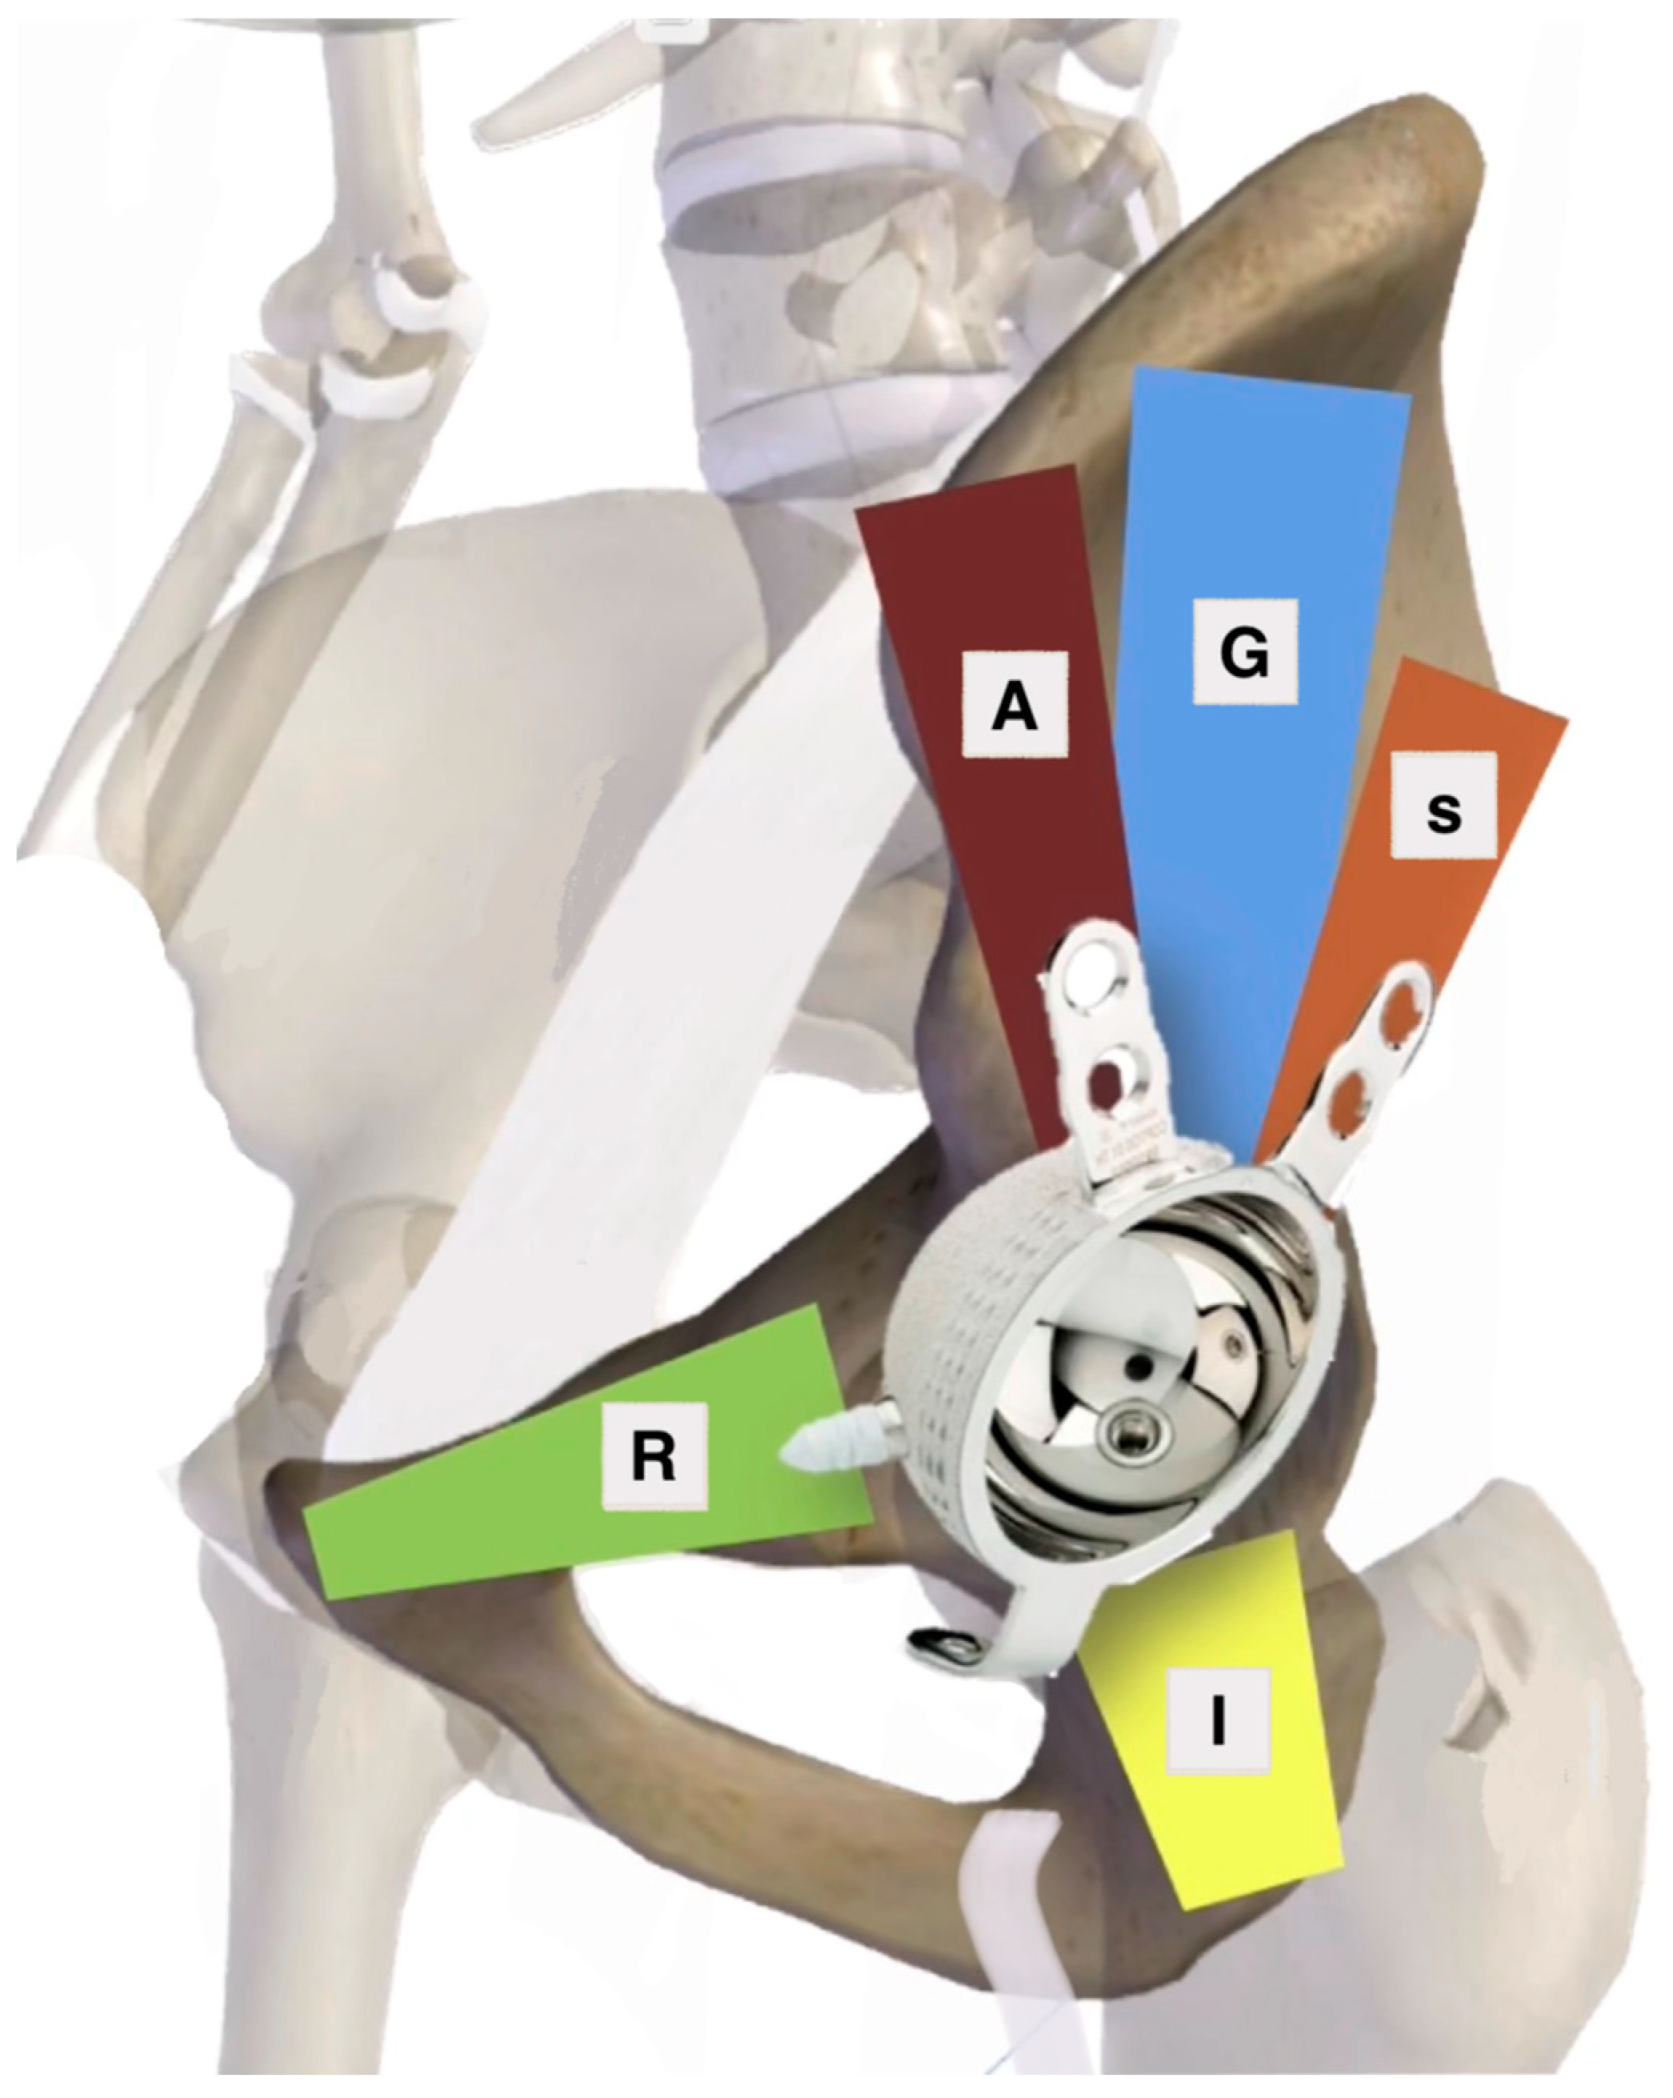

- T Marmor, M.; Huang, A.; Knox, R.; Herfat, S.; Firoozabadi, R. Mapping of the Stable Articular Surface and Available Bone Corridors for Cup Fixation in Geriatric Acetabular Fractures. J. Am. Acad. Orthop. Surg. 2020, 28, e573–e579. [Google Scholar] [CrossRef]

| 1. Zone of Articular Surface Fully or Partially Connected to Stable Bone | 2. Bone Stock Available for Screw Fixation |

|---|---|

| D—Dome zone only P—Posterior zone only A—Anterior zone only DP—Dome and posterior DA—Dome and anterior DAP—All zones | R—Superior ramus pubic corridor A—Anterior corridor G—Gluteal pillar corridor S—Sciatic buttress corridor I—Ischium corridor |